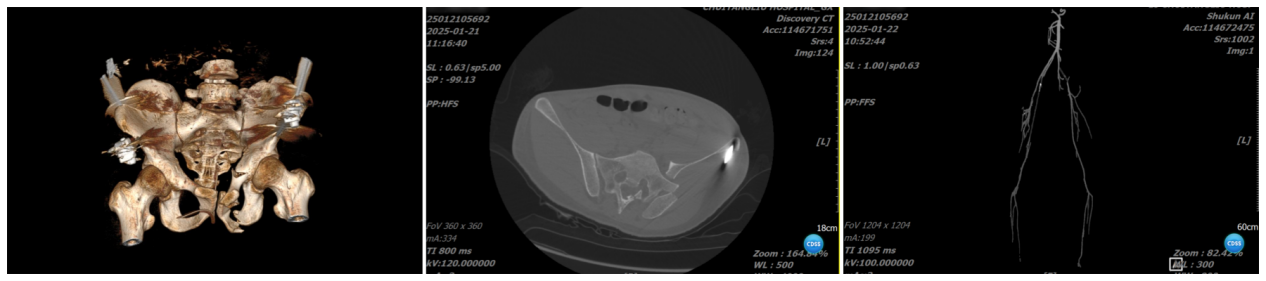

▲术前检查

入院后,创伤骨科(骨一科)医疗团队立即进行术前检查,发现患者血红蛋白仅为6.8g,贫血严重,考虑因多发骨折急性失血造成。输血科医生陈齐、潘裕莹在血库血量告急的情况下,紧急联系通州血站,为患者输入红细胞纠正贫血。为确保患者手术安全,徐执扬启动MDT多科室会诊,邀请介入与血管外科主任杨永久、麻醉科主任杨彦伟、病区护士长陈蕾会同重症医学科(ICU)、输血科以及科室医师共同讨论、制定治疗方案。